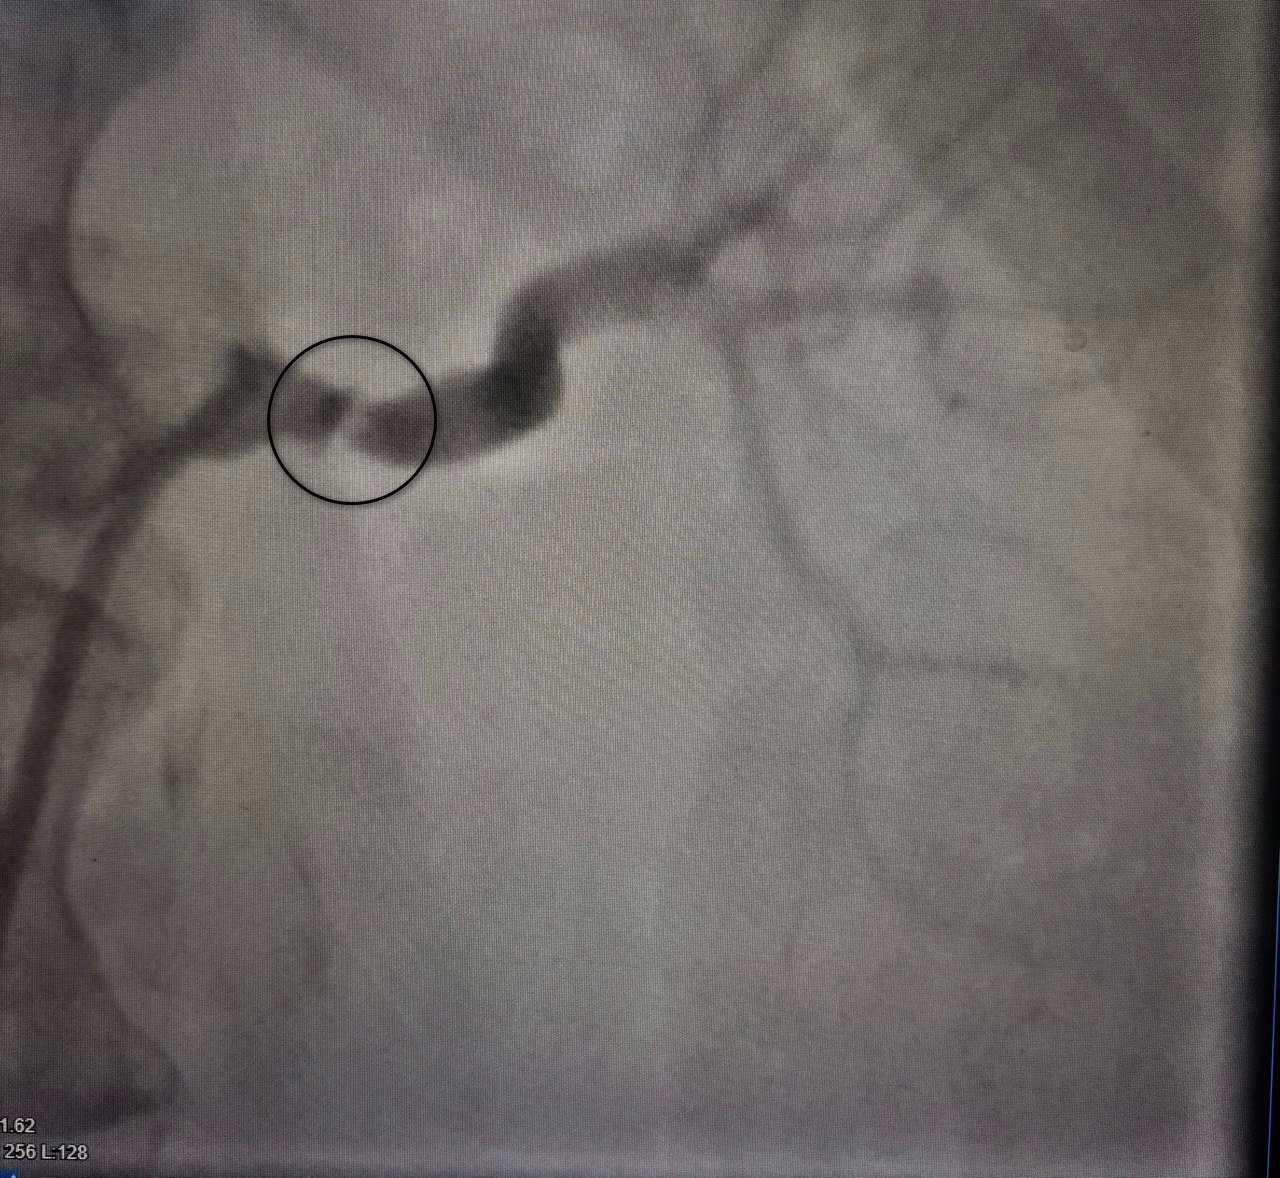

Врачи провели КТангиографию брюшной полости. Этот точный метод позволил детально изучить сосудистую систему и оценить состояние артерий в реальном времени.

Результаты исследования выявили критическую патологию — стеноз (сужение) левой почечной артерии до 80 %. Такая патология встречается редко — на нее приходится до 5 % всех случаев гипертонии.